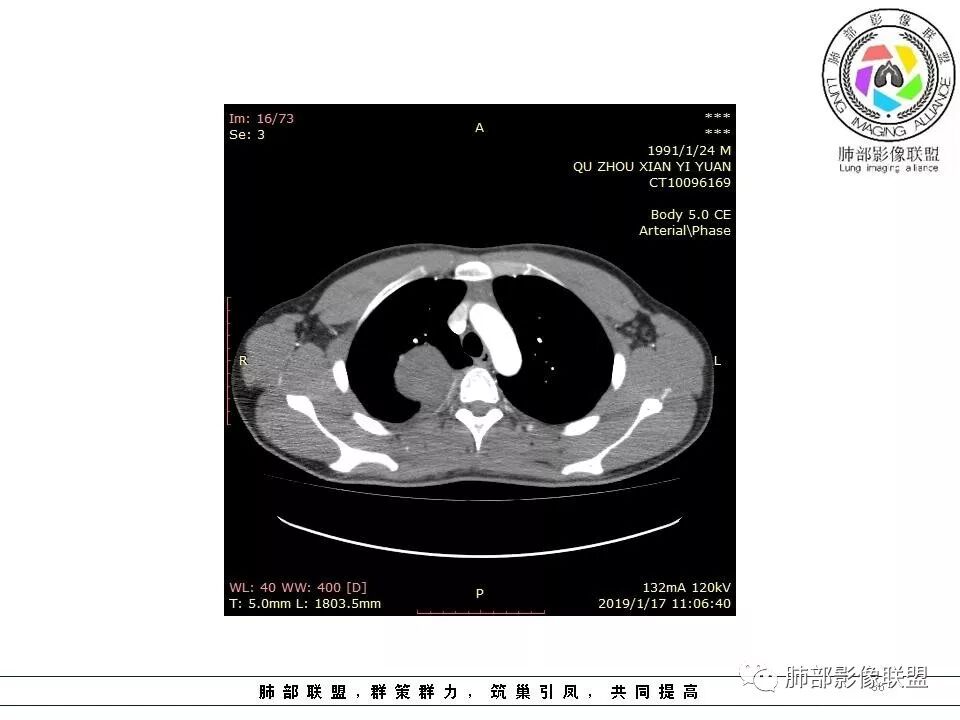

青年男性,间断胸痛;右侧脊柱旁可见一类圆形软组织密度影,密度欠均匀,增强扫描呈轻中度持续强化,邻近肺组织及肺动脉推移,可见肋间动脉供血,部分胸膜下脂肪可见,部分层面似见与右侧椎间孔相连。考虑后纵隔神经源性肿瘤。

青年男性,间断胸痛。右后纵膈脊柱旁软组织占位,形态规则类圆,边缘光整,肺组织受压,D字征,胸膜尾,肋间动脉供血。中度不均匀延迟强化。无支气管进入考虑来源于肺外、肿块与脊柱间未见明显脂肪间隙,考虑来源于胸膜外,考虑神经源性肿瘤,建议穿刺活检。

青年男性,右侧脊柱旁软组织肿块,边缘膨隆,密度不均,临近肺组织受压、胸膜增厚,增强后动脉期呈不均匀强化,并可见肋间动脉供血,延迟期强化较均匀,定位肺外,首先考虑SFT,神经源性肿瘤待排

右肺占位,跨越上叶后段、下叶背,边缘光滑,瘤肺界面清,见肺压缩缘(线样不张`强化),见胸膜尾征,胸膜下脂肪未见明显增厚,肋骨丶脊柱未见侵袭及受压,渐进性丶地图样强化,冠状位似见体循环供血

青年男性,右后上纵隔脊柱旁沟可见团状软组织影,边界清,密度尚均匀,推挤邻近肺组织,胸膜可见掀起,有肺动脉供血,增强轻度蛇皮样强化,纵隔淋巴结未见肿大,邻近骨质未见破坏,胸膜下脂肪间隙消失,考虑SFT孤立性纤维瘤可能性大,鉴别神经鞘瘤,节细胞瘤,建议活检。

边缘光滑,宽基底与胸壁相连,跨叶裂,叶裂稍前推,血管、支气管前移。

胸膜下脂肪间隙?

供血,体外供血,体循环,要么是壁层胸膜,要么胸膜外的,脏层胸膜应该是对内供血。病变里面的血管,除非是非常粗大迂曲的血管,不然,我不认为是其特点。

脏层胸膜肺内供血,壁层胸膜体外供血

脏层胸膜主要由支气管动脉和肺动脉供血,壁层胸膜主要由支气管动脉,胸廓内动脉、肋间动脉供血

1.右上胸内脊柱旁类圆形肿块,质地似乎比较坚实,密度稍显不均,但未显示明确的坏死。

2.肋间动脉病供血也提示肿块来自后纵隔?

3.相邻椎间孔未见扩大,也未见块影延入椎管,易起自于神经根的鞘瘤似乎找不到支持点。